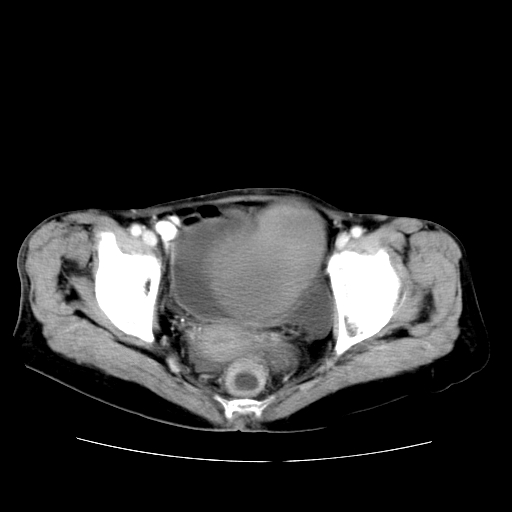

女性,72岁。

主诉下腹部坠痛不适1年余。

子宫增大如孕3月大小,质软,活动可,无压痛。

b超提示:盆腔(子宫前方)低回声团块。

临床诊断:盆腔肿块查。

1、这个肿瘤密度均匀,增强后轻中度均匀性强化,与左侧附件关系密切,肿瘤边缘光整、清晰。

2、左侧卵巢增大呈8×8×10cm大小,实性,表面光滑,边清,左侧输卵管爬行于左卵巢上,子宫萎缩。右输卵管、卵巢萎缩。

3、病理号:092658

左侧卵巢纤维瘤(性索间质肿瘤)

卵巢纤维瘤为良性卵巢性索间质肿瘤,常为单侧发病,当合并腹水或胸腹水时称麦格斯(meigs)综合征,肿瘤切除后胸腹水可消失。ct表现为盆腔内边界清楚的圆形或椭圆形肿块,常有分叶或不规则;肿瘤多为实性,少数为囊性、囊实性,完全囊性者可见壁结节。实性部分与子宫等密度;增强扫描常为轻度强化或几乎不强化。